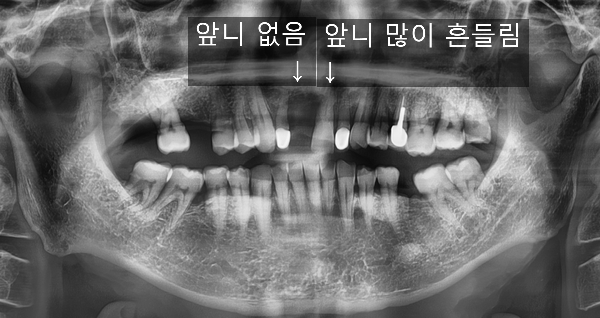

이 환자분의 경우

대문이(앞니) 중 하나가 없고, 다른 하나는 많이 흔들리는 상태였습니다.